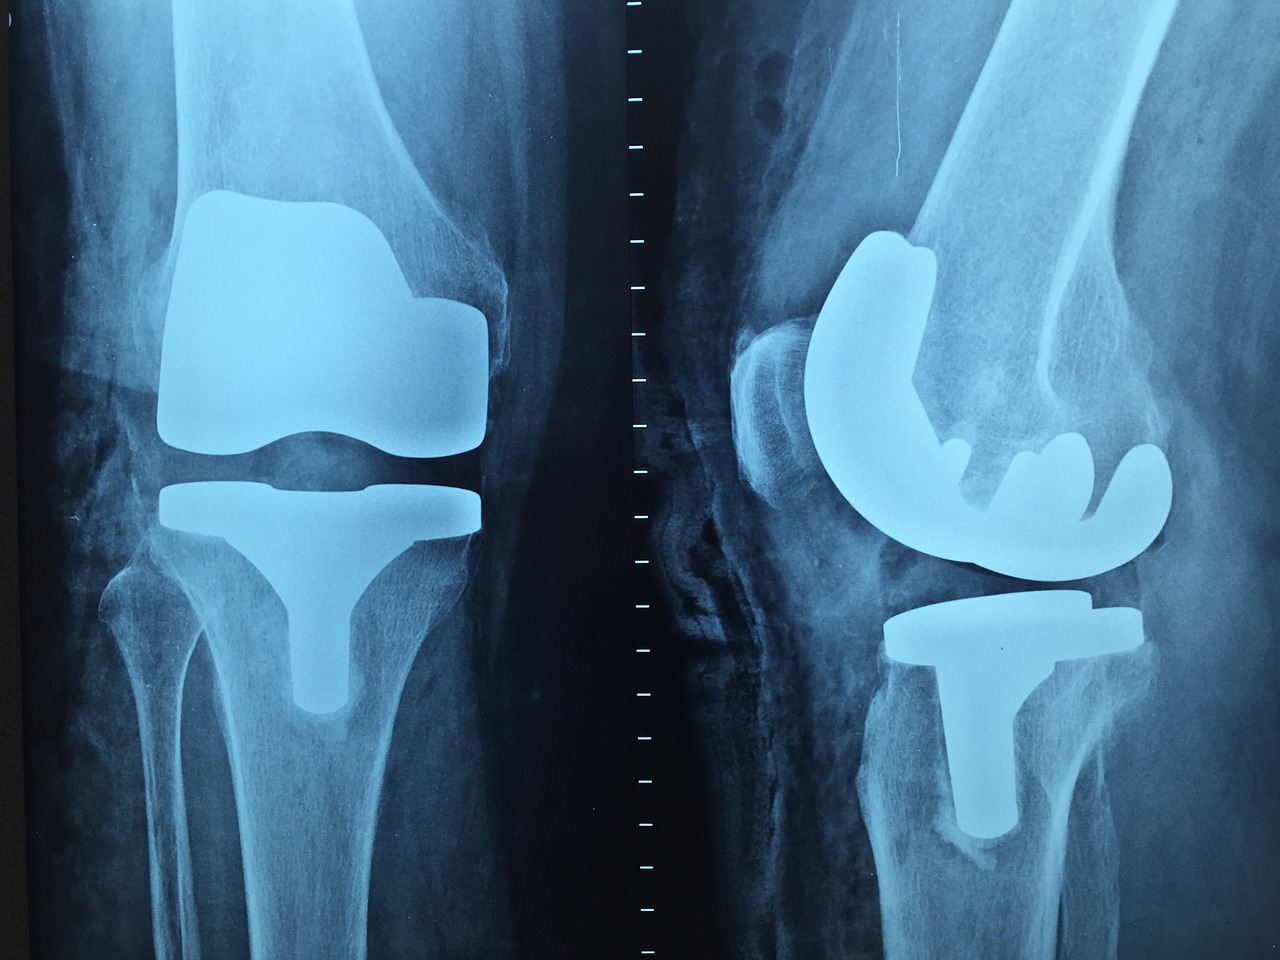

전치환술 (Total Knee Replacement, TKR)

이 수술은 무릎 관절의 모든 부분을 인공 관절로 교체하는 것을 말합니다.

퇴행성 관절염, 류마티스 관절염, 외상 등으로 인해 무릎 전체의 연골이 손상된 경우에 시행됩니다.

수술 후 통증 감소와 함께 관절의 기능이 향상되어 일상 생활이 용이해집니다.

전치환술은 특히 노년층에서 많이 시행되며, 효과적인 결과를 보여줍니다.

반치환술 (Partial Knee Replacement, PKR)

이 수술은 무릎 관절의 일부분만 인공 관절로 교체하는 것을 말합니다.

보통 퇴행성 관절염이 무릎의 일부분에만 영향을 미칠 때 시행됩니다.

전치환술에 비해 수술 시간이 짧고 회복이 빠르며, 더 자연스러운 느낌을 유지할 수 있습니다.

그러나 다른 부분에도 퇴행성 관절염이 진행될 가능성이 있어, 장기적인 관점에서는 전치환술보다 수명이 짧을 수 있습니다.